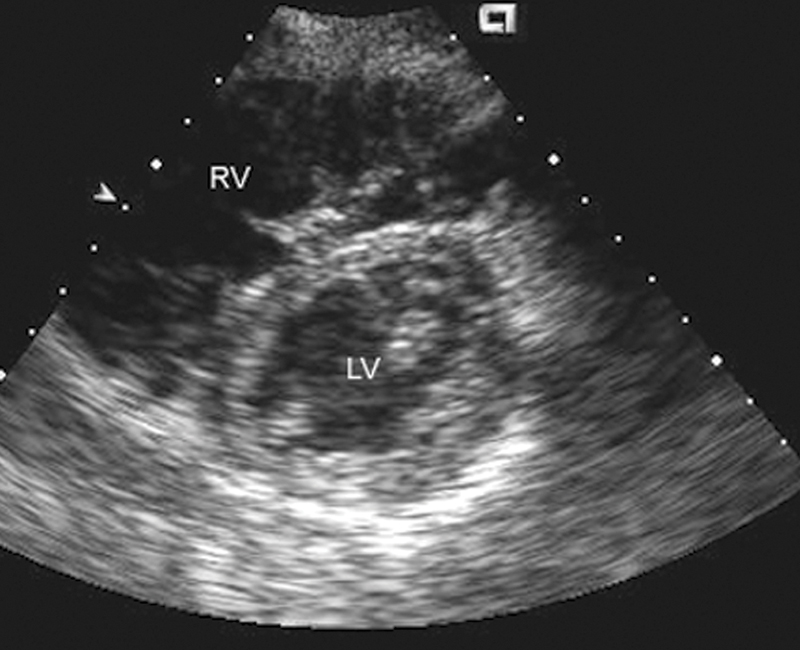

فحوصات تشخيصية لبعض امراض القلب والشرايين التاجية